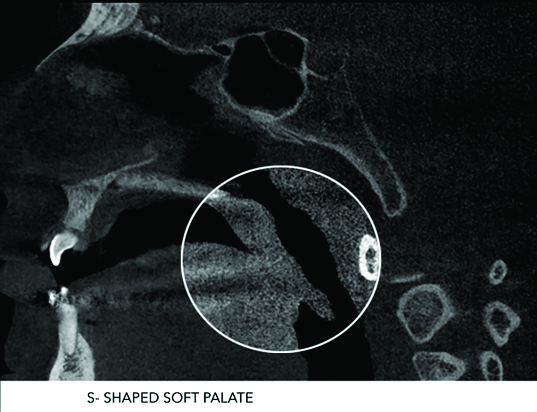

Various studies have been done to study morphological variations of soft palate using lateral cephalogram. In the study done by You et al., [3], the morphological variations were classified into six types (Type 1: Leaf shaped; Type 2: Rat tail; Type 3: Butt like; Type 4: Straight line; Type 5: S-shaped and Type 6: Crook shaped). Pepin et al., reported that the “Hooked or S-shaped” soft palate indicated a high risk of the obstructive sleep apnoea syndrome [4]. According to Subtelny, Need’s ratio is pharyngeal depth to velar length which ranges from 0.6 to 0.7 in normal population, if it increases, concern group may have a risk of VPI (Velopharyngeal incompetency) [5].

One hundred and twenty one scanned full volume CBCT images recorded by digital radiographic machine (Kodak CS9300, Carestream Health Inc., Rochester, NY) with a tube potential of 90 kV, a tube current of 5 mA, Voxel size of 300μm and an exposure time of 11.30 seconds were included. All the scans were taken with the patients standing upright in a natural head position and were instructed to contact their molars and breathe through their nose. All the scans were analysed and categorized into six types according to the soft palate morphology by an oral and maxillofacial radiologist [Table/Fig-1,2,3,4,5 and 6].

In this study, 121 subjects that included 67 males (55.4%) and 54 females (44.6%) were studied for evaluation of the morphological variants and types of soft palate observed in CBCT images. The mean age and standard deviation (SD) of all subjects were 27.23 ± 10.33 years. All the scans were interpreted for soft palate morphology and following six shapes were identified i.e. Rat tail, Butt shape, Leaf shape, Handle shape, S-shape and Crook shape.

S-shaped soft palate was seen in 9.9% of the cases in the present study, while it was observed in 4.7% cases in study done by Verma et al., [1], 3.5% o cases were detected in study done by You et al., [3], inferencing that Central Madhya Pradesh population have greater chances of having Obstructive Sleep Apnoea Syndrome (OSAS).